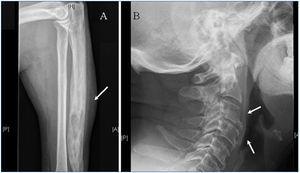

En mayo de 2011, se realiza tomografía computarizada para inclusión en lista de espera de trasplante renal y se objetiva una lesión esclerosa en el hueso ilíaco derecho. Posteriormente la gammagrafía ósea muestra un incremento en la captación del radiotrazador en columna cervical, primer dedo de mano derecha, cúbito izquierdo, articulación sacro-ilíaca derecha y, de menor intensidad, en maléolo externo del tobillo izquierdo, y en la serie ósea se confirma la presencia de lesiones esclerosas en columna cervical, cúbito izquierdo y articulación sacro-ilíaca derecha (figura 1).

Figura 1. Enfermedad de Paget en enfermedad renal crónica